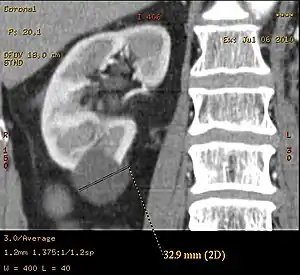

Renal cyst of the left kidney (hyperintense area) as shown on MRI. | |